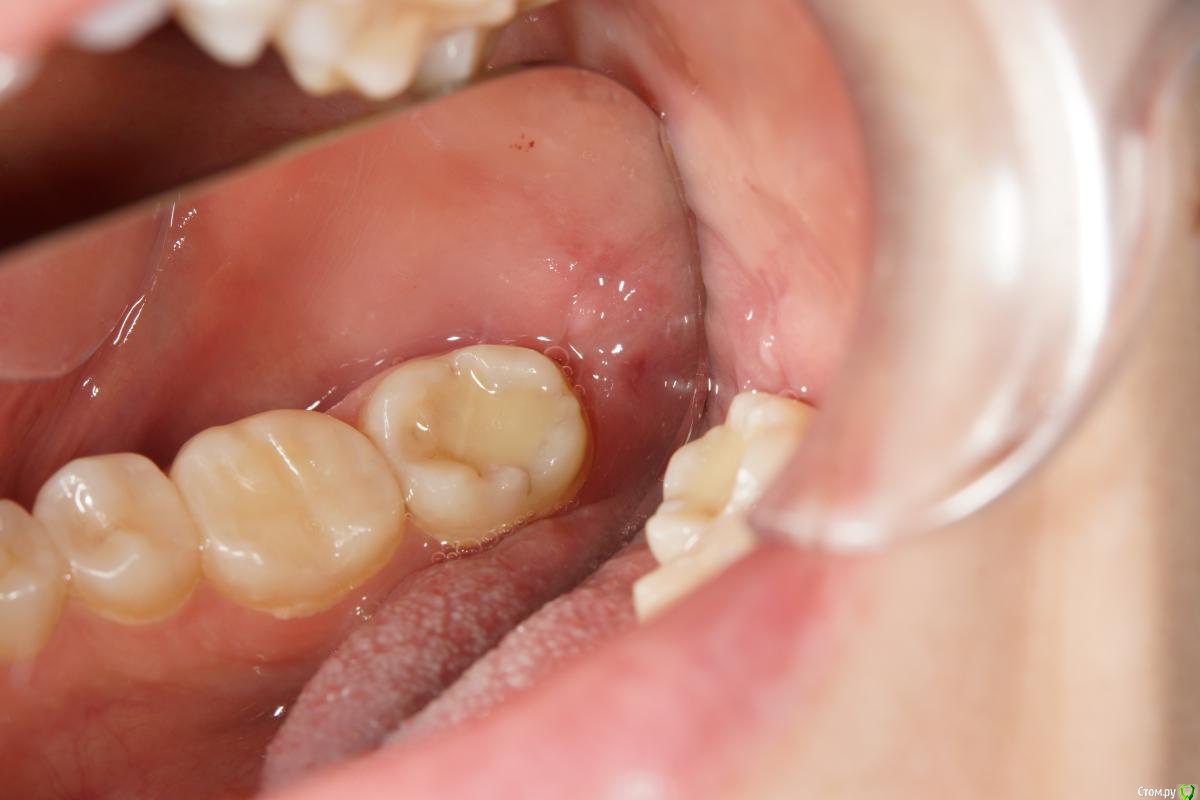

колесников Опубликовано 31 октября, 2017 Автор Поделиться Опубликовано 31 октября, 2017 Ещё раз о закрытии лунки нижних 3их моляров. В лунке 0.5 г графта ,Выделен ретромолярноязычный лоскут и зафиксирован вестибулярно. Края лунки сведены после мобилизации и ушиты двойными узловыми швами. Со слов пациентки болезненность только в день удаления,далее течение бессимптомное. Судя по желтизне кожных покровов шеи,была гематома.Швы удалены через неделю,отмечается расхождение краев,нижний лоскут стабилен,герметичность сохранена. Отправлена на домашнее долечивание с антисептическими повязками. Итого: 1 визит. 3 Ссылка на комментарий

BORA Опубликовано 31 октября, 2017 Поделиться Опубликовано 31 октября, 2017 Ещё раз о закрытии лунки нижних 3их моляров. В лунке 0.5 г графта ,Выделен ретромолярноязычный лоскут и зафиксирован вестибулярно. Края лунки сведены после мобилизации и ушиты двойными узловыми швами. Со слов пациентки болезненность только в день удаления,далее течение бессимптомное. Судя по желтизне кожных покровов шеи,была гематома.Швы удалены через неделю,отмечается расхождение краев,нижний лоскут стабилен,герметичность сохранена. Отправлена на домашнее долечивание с антисептическими повязками. Итого: 1 визит.Здравствуйте.Хороший метод,спасибо за кейс.Вы пробовали использовать грануляционную ткань,таким же методом,которая образуется в дистальной области лунки при хроническом воспалении? Ссылка на комментарий

Kazankov.Egor Опубликовано 2 июня, 2018 Поделиться Опубликовано 2 июня, 2018 Ещё раз о закрытии лунки нижних 3их моляров. В лунке 0.5 г графта ,Выделен ретромолярноязычный лоскут и зафиксирован вестибулярно. Края лунки сведены после мобилизации и ушиты двойными узловыми швами. Со слов пациентки болезненность только в день удаления,далее течение бессимптомное. Судя по желтизне кожных покровов шеи,была гематома.Швы удалены через неделю,отмечается расхождение краев,нижний лоскут стабилен,герметичность сохранена. Отправлена на домашнее долечивание с антисептическими повязками. Итого: 1 визит.Откуда начинаете выкраивать лоскут? Как избежать травмы язычного нерва? Ссылка на комментарий